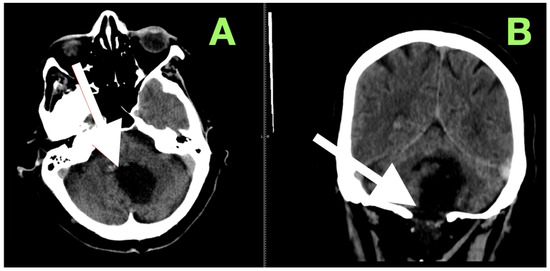

High-resolution MRI with selective MRA was obtained immediately after the examination to determine the spatial extent of the mass, vascular relationships to it, and to evaluate the current status of cerebrospinal fluid dynamics. Sagittal MRA reconstruction (Figure 1) revealed a large extra-axial mass in the left posterior fossa that centered on the cerebellar hemisphere and extended medially into the vermis. Posterior fossa arteries were lengthened and changed their course: the posterior inferior cerebellar artery (PICA) appeared to follow an elongated superior–posterior course along the dorsal surface of the mass with maintained continuity and caliber, the anterior inferior cerebellar artery (AICA), and small cerebellar perforators were also pushed to the left but appeared to be unaffected. The gradual vascular displacement without distortion, alteration, or irregularity would be consistent with chronic adaptive remodeling of the vessels; acute distortion did not occur, and there was no vascular blush, arteriovenous shunt, and/or feeding-vessel hypertrophy, identifying the extra-axial mass as an avascular, space-occupying lesion consistent with an epidermoid tumor.

Figure 1. Preoperative magnetic resonance angiography, sagittal reconstruction, demonstrating a large extra-axial mass in the left posterior fossa centered in the cerebellar hemisphere with medial extension toward the vermis. The lesion produces smooth elongation and displacement of adjacent posterior fossa arteries, most prominently the posterior inferior cerebellar artery (PICA, white arrow), which is draped over the superior–posterior surface of the mass. Vessel continuity and caliber are preserved, indicating chronic adaptive displacement rather than acute encasement or invasion. The absence of abnormal vascular blush or arteriovenous shunting supports the impression of an avascular lesion, consistent with the imaging profile of an epidermoid tumor.